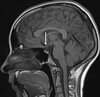

3

Q

A

body of corpus callosum